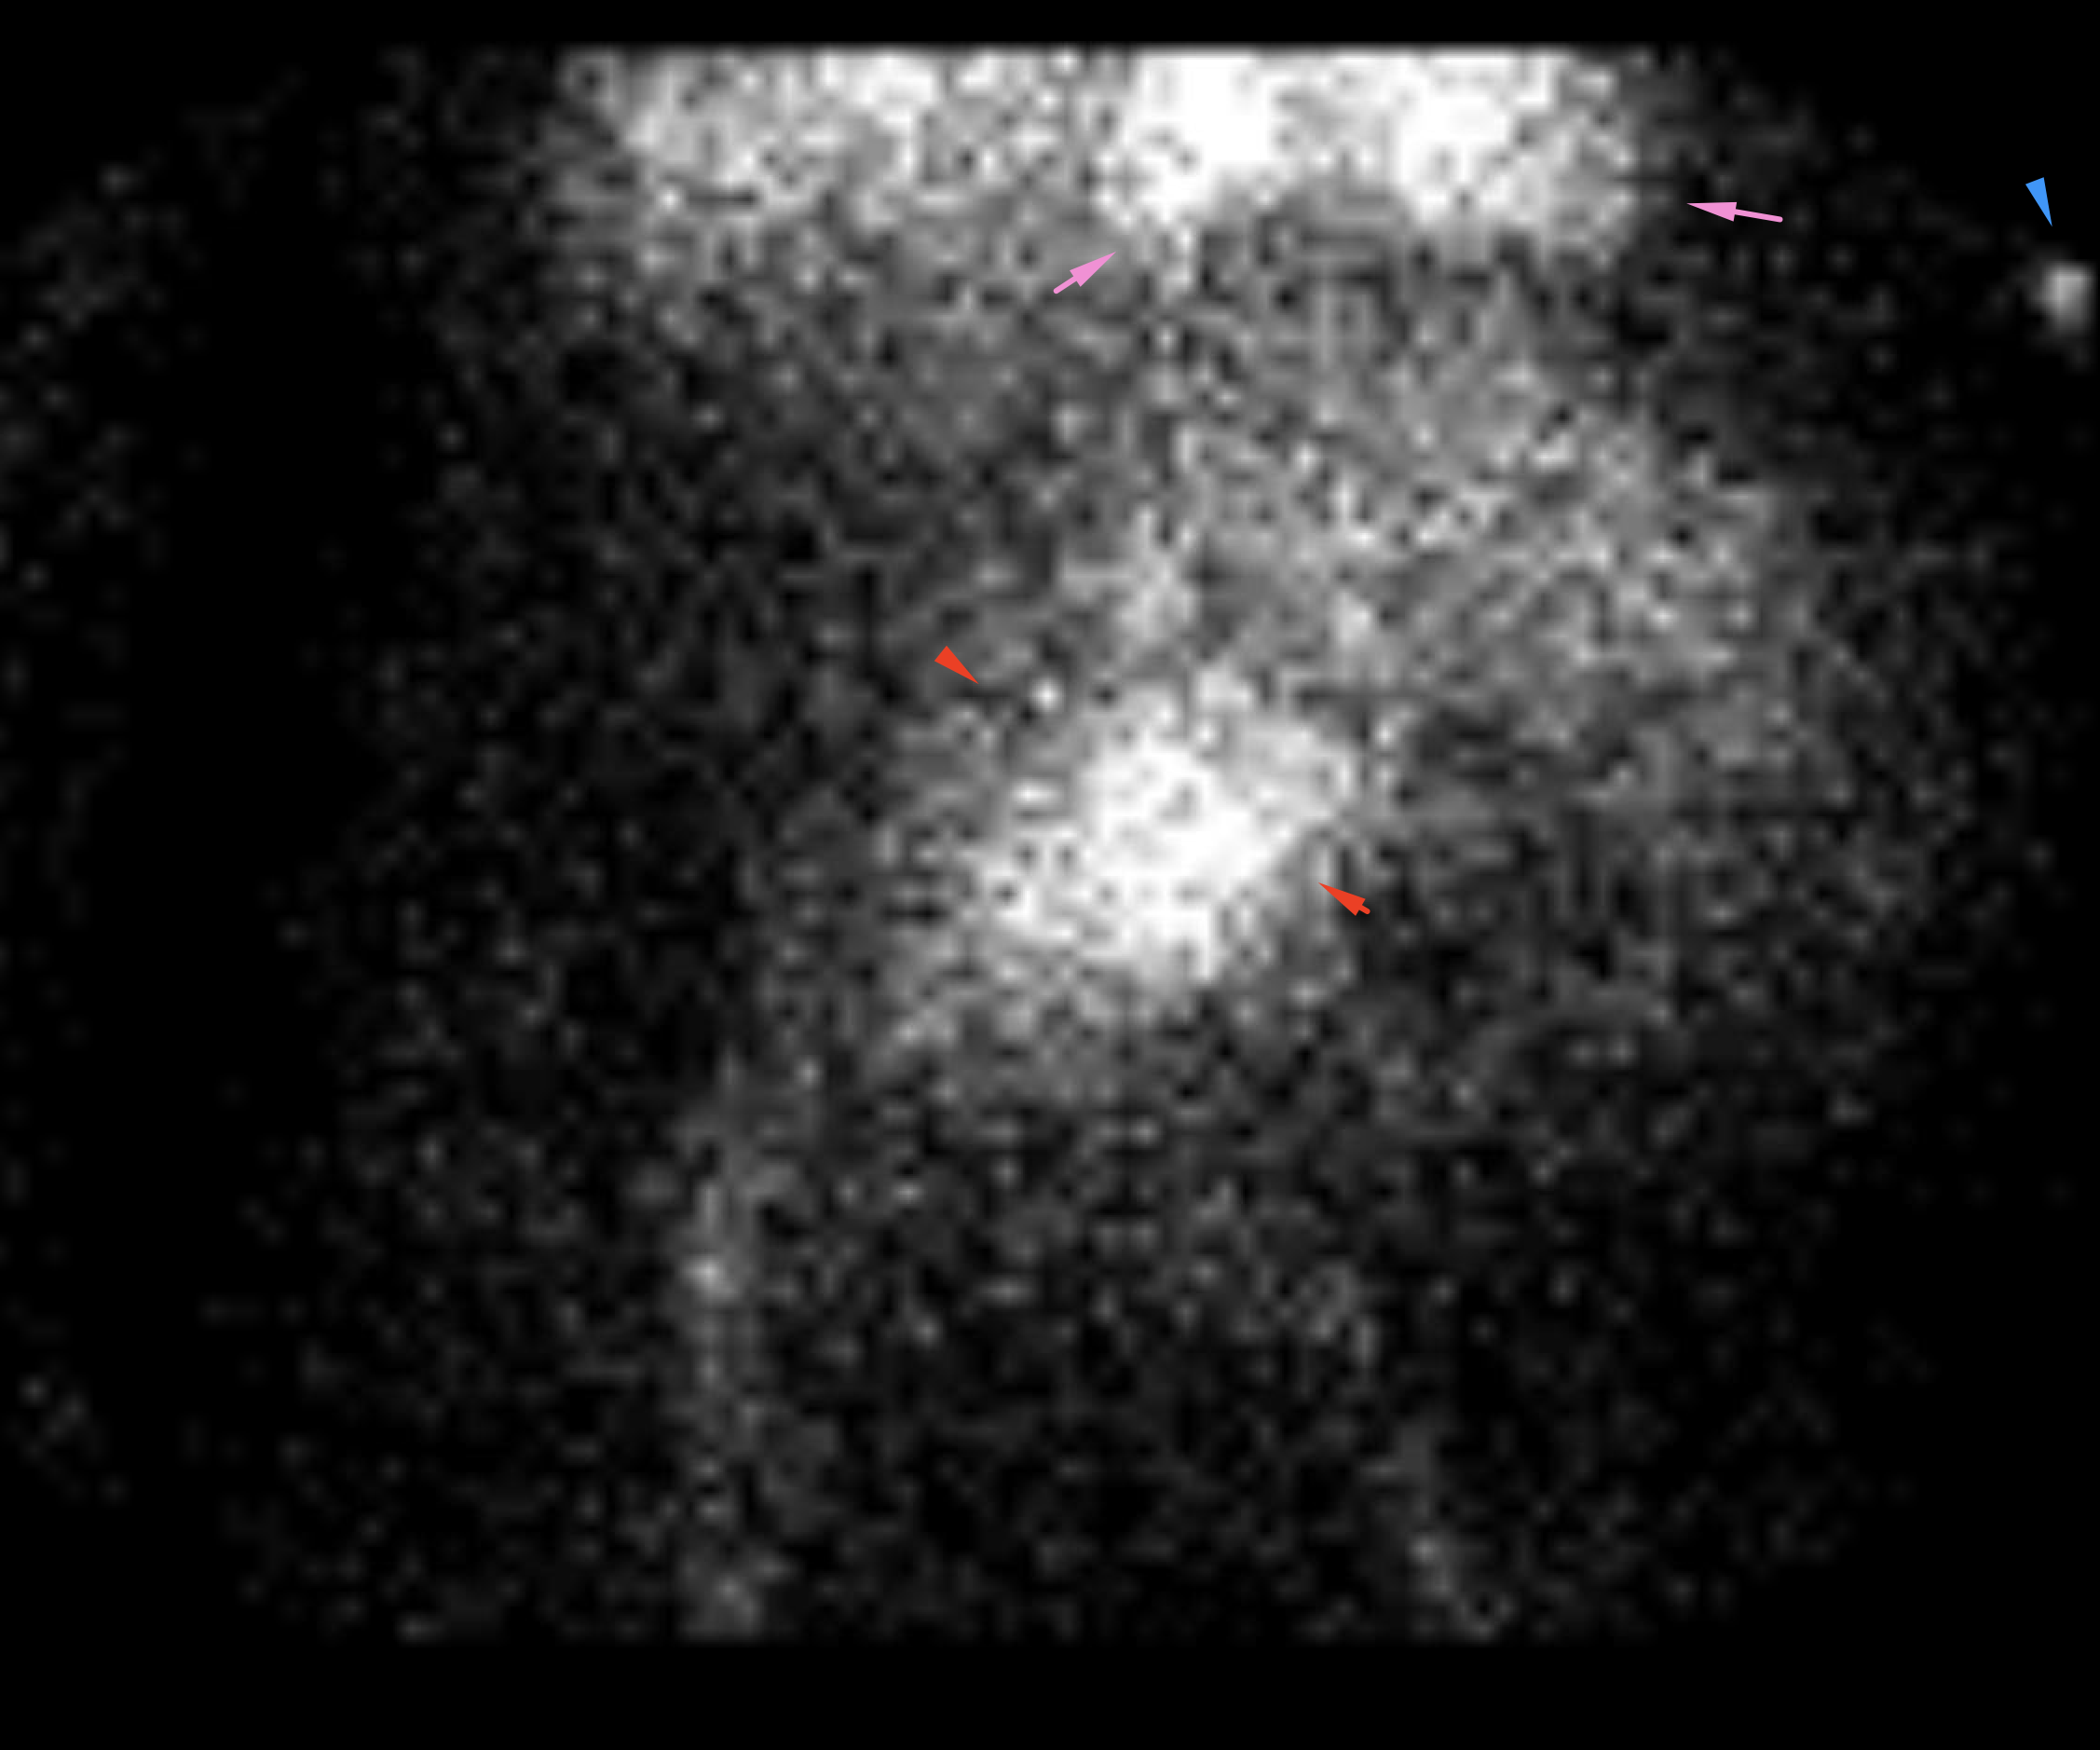

Age: 75

Sex: Female

Indication: Bright red blood per rectum, history of diverticulosis

Radiotracer: Tc99m labeled RBCs

Sample ReportNo evidence of active GI bleeding during the course of this exam.

Abdominal aortic aneurysm. Recommend CT or ultrasound for further assessment.